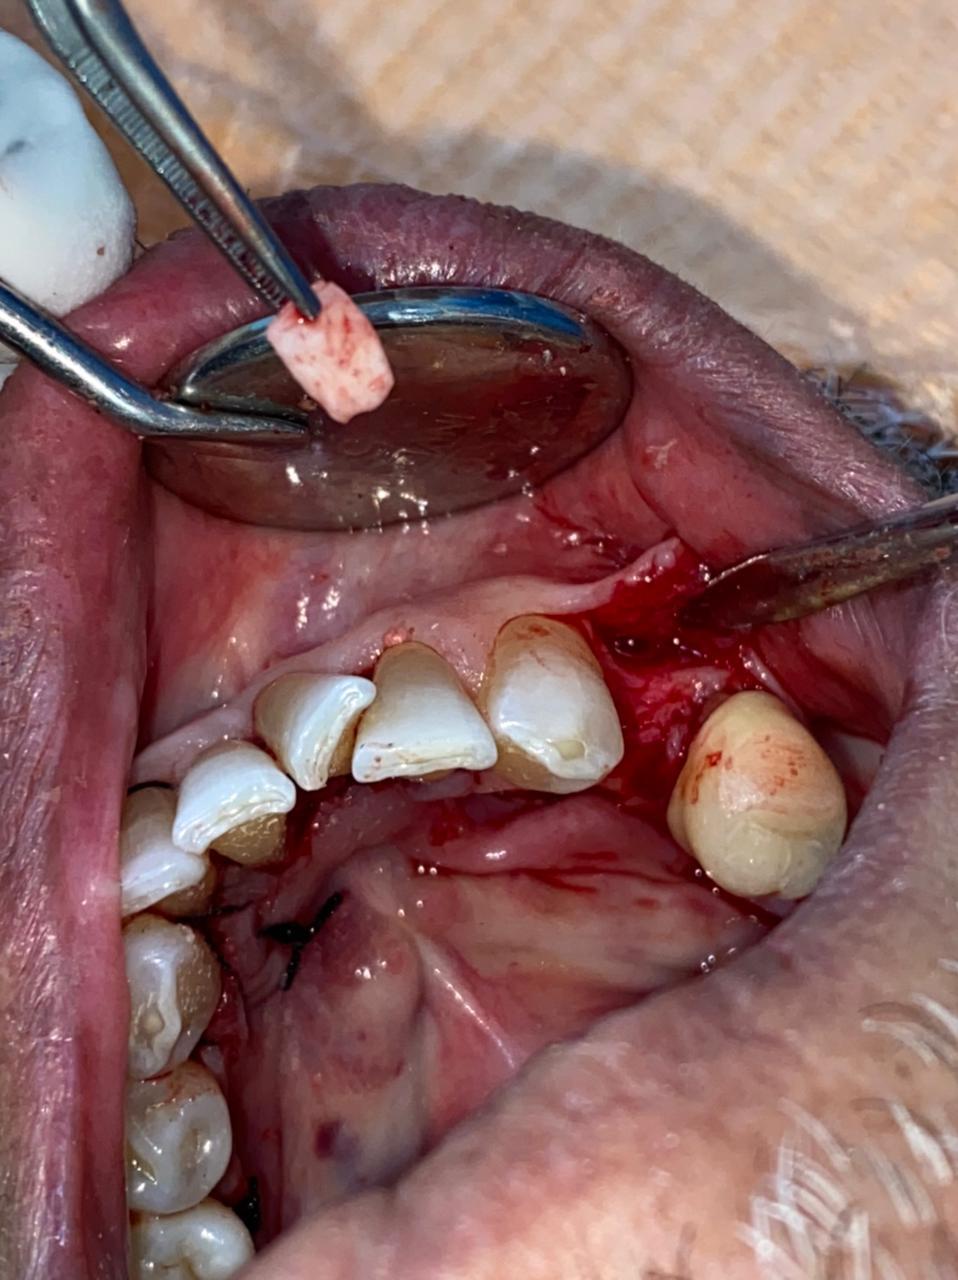

Paciente femenina de 25 años de edad, que se presenta con crecimiento de tejido blando en cuadrante I, a nivel de superficie de 15, 14,13,12,11. con protusión facial y compromiso de ala nasal del hemicara derecha.

Desde hace varios años, se envía para la realización de endodoncia en piezas mencionadas y posteriormente se efectuara exéresis de tejido blando intraoralmente.

Sistémicamente sana, exámenes no reportan anomalía y radiografías presentan lesión radiolucida en cuadrante I.

Se observa surco nasolabial derecho, comprometido (borrado), tercio medio de hemicara derecha, edematizado y protruido, asimetría facial marcada.

Lado afectado con forma leonina. Estima del paciente sumamente bajo, esquiva a la toma de fotografías.

Realización de endodoncia en piezas 15 hasta 11 previo a la cirugía.

Exéresis de lesión radicular.

Remitir espécimen a biopsia.

Controles quirúrgicos.

Mucosa vestibular alveolar levemente con cambio de coloración, se palpa en fondo de vestíbulo masa indurada, poco dolorosa y de consistencia fibrosa.